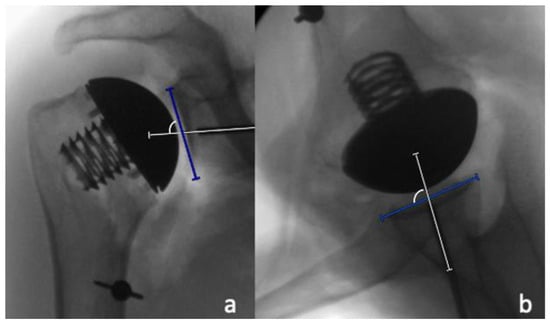

2.2. Radiographic Analysis

Radiographic analysis was performed by two independent reviewers (LC and MM) who were not involved in the surgeries performed, and who were blinded to which case had performed, utilizing a deltopectoral or a PI approach. All measurements were performed with the image analysis software Visage 7.1 (Visage Imaging, Berlin, Germany). The preoperative and postoperative neck-shaft angle (NSA) was determined on pre- and postoperative AP radiographs, as previously described by Flurin et al. [16] (Figure 4). For the determination of the native center of rotation (COR) on the postoperative AP radiographs, a best-fit circle was placed based on three preserved bony landmarks, as previously described [17,18]: (1) the lateral cortex of the greater tuberosity; (2) the medial calcar at the inflection point; and (3) the medial footprint of the rotator cuff on the greater tuberosity. A second implant-matched circle was then placed to fit the curvature of the prosthetic humeral head. The COR from each circle was then identified, and a coordinate system was generated from the native COR, with the y-axis aligned parallel to the intramedullary axis of the shaft, and the x-axis as perpendicular to the shaft. The deviation between the pre- and postoperative COR was then determined in the x- and y-axis [18]. In the x-coordinate plane, a shift of postoperative COR was medially considered as positive, and a shift laterally negative, while in the y-coordinate plane, a superior shift was considered as positive, and an inferior shift, negative. The measured distance between the native and the postoperative COR in the medio-lateral and the supero-inferior directions were then each divided by the diameter of the native best-fit circle, and were reported as a percentage (Figure 5a). In addition, the shift between the pre- and postoperative COR in anteroposterior direction was determined on axillary radiographs in a similar fashion. A best-fit circle was fitted on the two edges of the humeral resection plane, with its COR corresponding to the middle of the resection plane. A second implant matched circle was then placed to fit the curvature of the prosthetic humeral head. The COR was then identified from each circle, and a coordinate system was generated from the anatomic COR, with the y-axis aligned parallel to the intramedullary axis of the shaft, and the x-axis perpendicular to this line, to measure the distance between both COR in the anteroposterior direction. In the x-coordinate plane, a shift of postoperative COR anterior was considered positive, and a shift posterior, negative. The measured distance between the native and postoperative COR in an anteroposterior direction was then divided by the diameter of the native best-fit circle, and was given as a percentage (Figure 5b).

Furthermore, the supero-inferior and antero-posterior size matching between the humeral resection plane and prosthetic humeral head diameter were determined and expressed as percentages by dividing the prosthetic head diameter by the length of the humeral resection plane in the AP and axillary radiographs, respectively (Figure 5c,d).

Figure 5. A best-fit anatomic circle (green circle) with its center of rotation (COR) (green x), and a best-fit implant circle (red circle) with its COR (red x) are placed on the AP (a) and axillary (b) views to determine the differences in the positioning of the COR. The length of the resection plane (green line) and the prosthetic humeral head (red line) were compared on the AP radiographs (c) and the axillary radiographs (d).